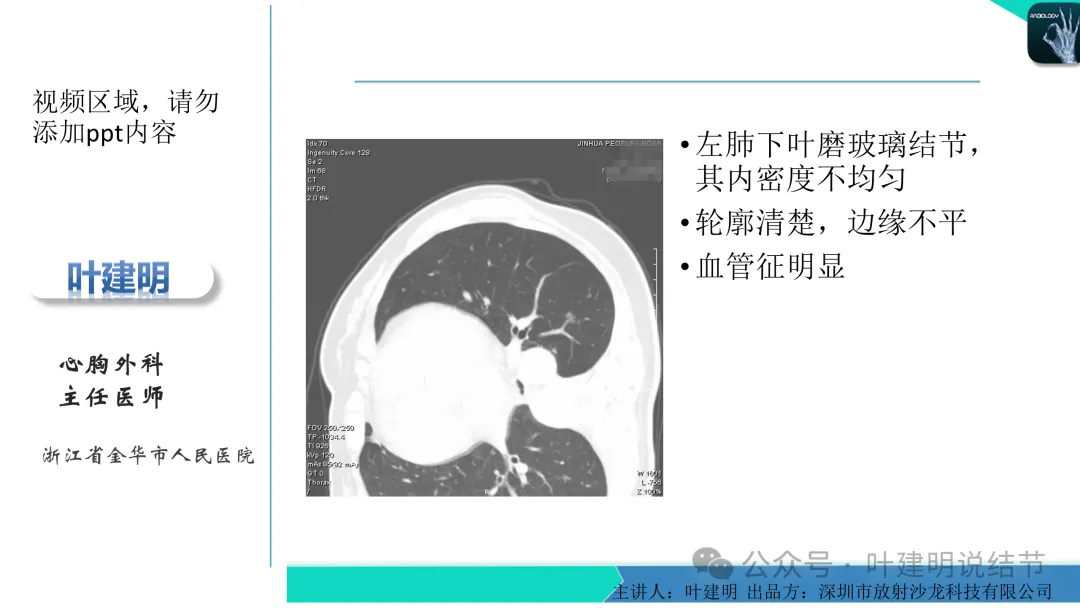

当地说考虑微浸润性腺癌的左下主病灶影像连续层面展示:

这个病灶会是微浸润性腺癌吗?当然没有病理诊断,我也不能说百分之百必不会,但这样的病灶已经风险大到必得尽快手术切除干预了吗?显然还早着呢:1、影像不是典型的结节状;2、边缘与轮廓模糊不清;3、灶内似有细支气管扩张(更容易是细支气管扩张伴少许周围炎或肺泡上皮增生);4、血管邻近走但无牵拉影响;5、没有实性成分,没有锐利毛刺,没有胸膜牵拉,没有血管进入,没有任何倾向风险性高的影像特点。我一直强调:肺结节是否要干预处理,不要纠结于最后病理是什么,而要看风险高低;而风险高低的最重要术前判断依据一是随访有无进展,二是有没有实性成分。只要没有肉眼可见的影像上的实性成分,风险就是低的!何况病理也是人看的,原位还是微浸润,不典型增生还是原位有时也在一念之间。

早在2020年时,我受邀在《放射沙龙》做过一个系列的精品课,当时专门总结分析过各类良恶性肺结节与肿块的影像特征,这是当时关于微浸润性腺癌影像特征的分析,今天看来仍基本不太需要改变,大家有兴趣的可以参考: